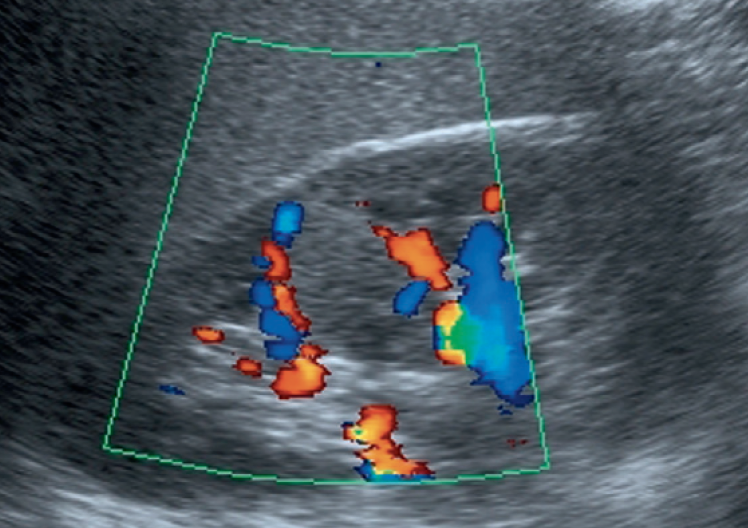

1-Hypertrophied column of Bertin

أعتقد بأن هذا من أهم المتغيرات التي قد يشتبه في كونها ورم. هي ببساطة تضخم لنسيج الكلية parenchyma إلى الداخل sinuses مرورا بين الأهرامات الكلوية medullary pyramids.

يميزه تناسق echogenicity بينه وبين باقي parenchyma بالإضافة لعدم وجود ارتفاع أو تغير ملحوظ في قراءات colour Doppler. غالبا لا يزيد عرضه عن ٣ سم.